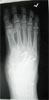

Progress

just before 2nd surgery to correct equinus(foot osteotomies)

Post

Op

Forefoot osteotomy done to correct fixed equinus in 2nd surgery with good result